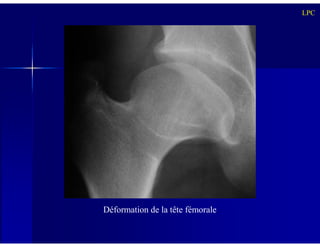

Déformation de la tête fémorale

Stade de séquelles:

LPC

- Coxa Magna, Coxa Plana, Coxa vara

- Découverture de la tête fémorale

- Col fémoral court et élargi

- Raccourcissement du membre homolatéral